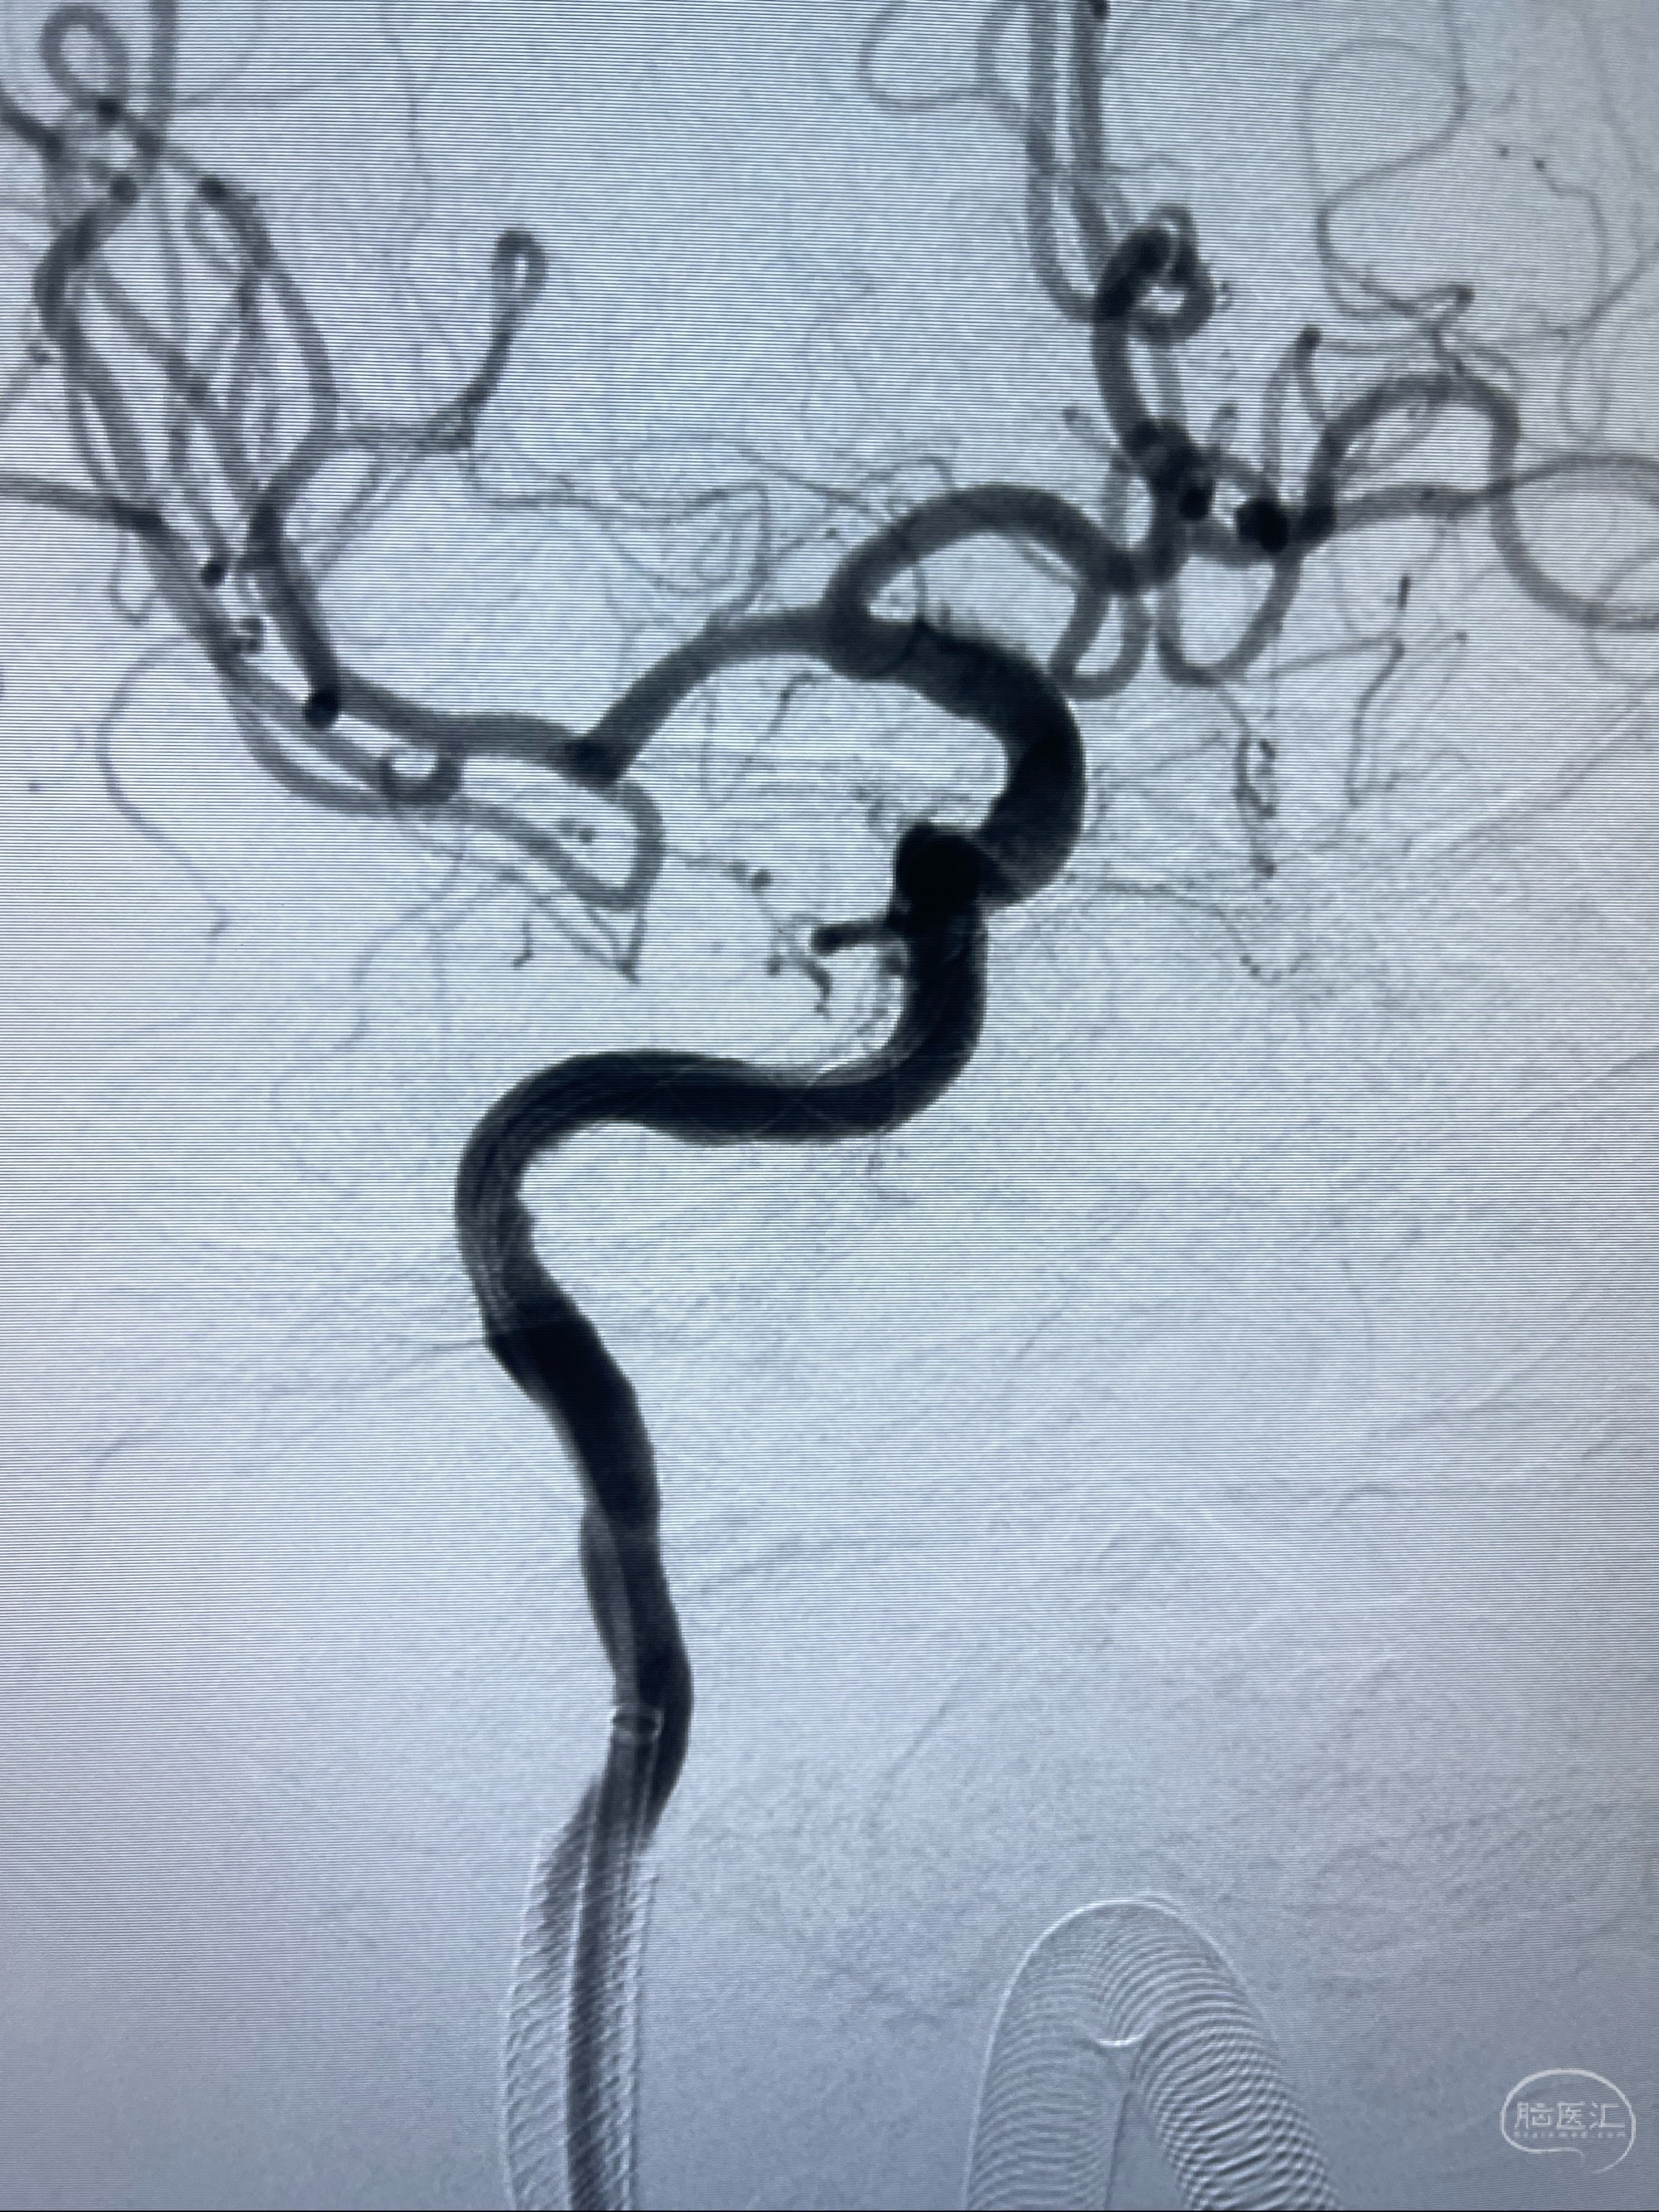

2023-07-10DSA:右侧颈内动脉岩骨段夹层伴中偏重度狭窄改变,左侧颈总动脉闭塞、右侧颈外动脉由右侧肋颈干甲颈干吻合代偿

箭头所示为颈内动脉岩骨段重度狭窄,结合MRI,考虑为肿瘤侵犯右侧颈内动脉

箭头以近至支架段管腔不规则狭窄

经导引导管造影显示支架远端颈内动脉不规则狭窄伴局部充盈缺损,同时行全身肝素化5ml